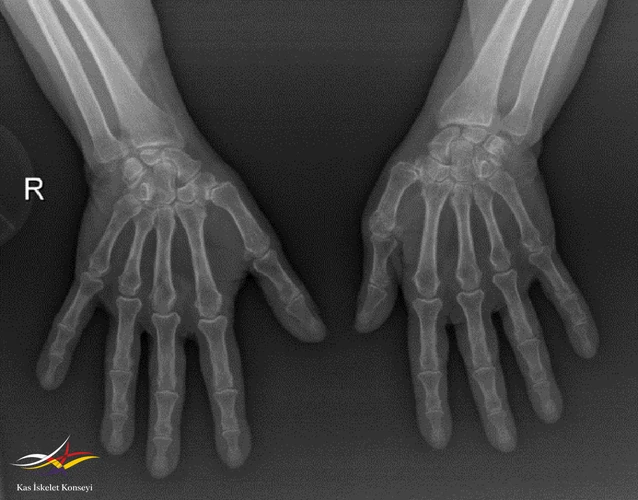

Resim 3. El grafisi.

Muayene: Sol omuz: Flex: 0-70°, Abd: 0-70°, İstirahatte VAS: 0, Hareket ile VAS:1-2, GYA’de bağımsız. Sistemik tutulum ve organ tutulumu yok. Diğer fizik muayene doğal ellerde deformite yok.

Ön tanıda romatoid artrite bağlı eklem tutulumu, avasküler nekroz, Charcot eklemi (periferik nöropati- servikal radikülopati?) olasılıkları tartışıldı.